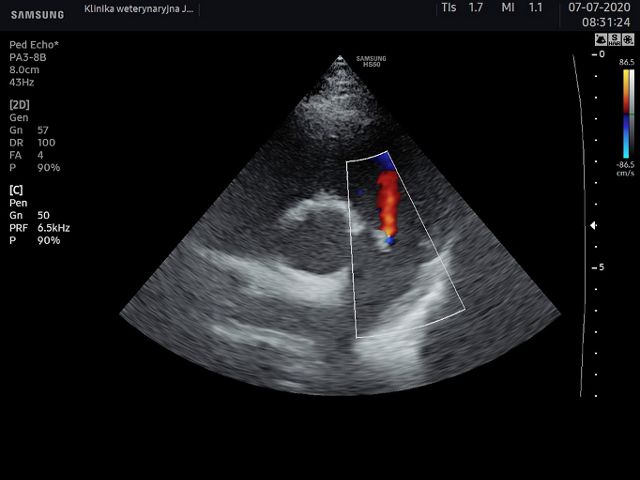

Dysponujemy wysokiej klasy aparatem ultrasonograficznym Samsung HS50 wyposażonym w funkcje Dopplera ciągłego, pulsacyjnego, kolorowego oraz tkankowego. Do dyspozycji mamy specjalistyczne sondy, w tym sondę convex, microconvex, liniową oraz sektorową kardiologiczną. Dla komfortu naszych pacjentów w gabinecie USG dysponujemy stołem o regulowanej automatycznie wysokości oraz specjalną nakładką do badania echokardiograficznego.